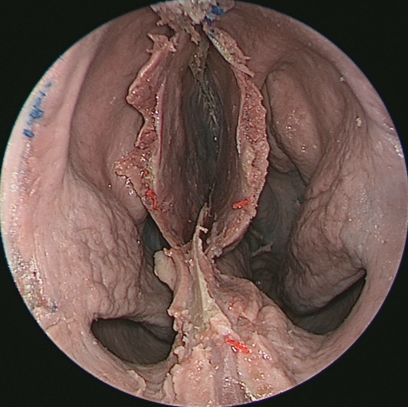

↑ 去除鼻中隔观察鼻腔后壁结构

抵近观察左侧右鼻孔 ↓